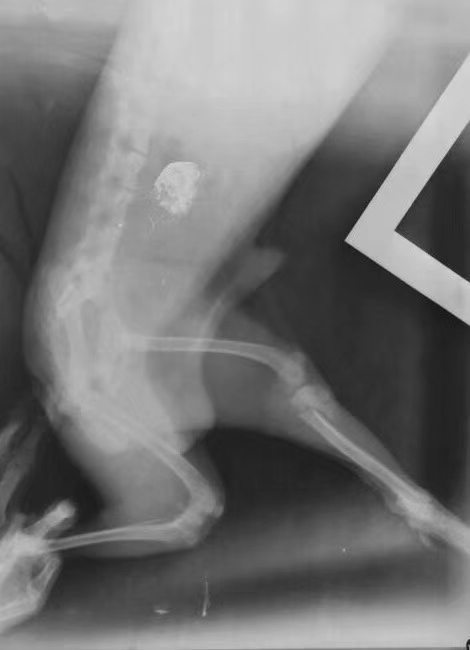

車禍/咬傷各一例: 泰迪,被車碾壓挫傷,導(dǎo)致皮膚開裂,骨折,實(shí)施緊急手術(shù)處理;約克夏,summer,溜狗時(shí)被大型犬咬傷于臀部,實(shí)施傷口清洗,壓迫縫合。Ps:  過年了,注意安全,注意安全,帶好牽引繩,保護(hù)好自家寶貝。